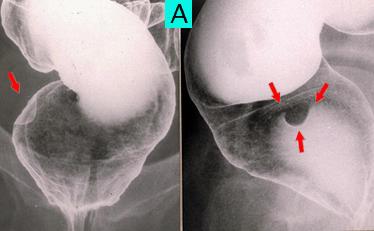

疾病(病理主体)的分类类癌肿瘤/

部位(按器官分)大肠/直肠

检查方法X线

肿瘤最大直径1~9

肿瘤的深度sm